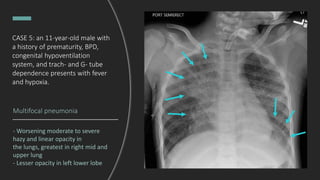

CASE 5: an 11-year-old male with

Multifocal pneumonia

- Worsening moderate to severe

hazy and linear opacity in

the lungs, greatest in right mid and

upper lung

- Lesser opacity in left lower lobe